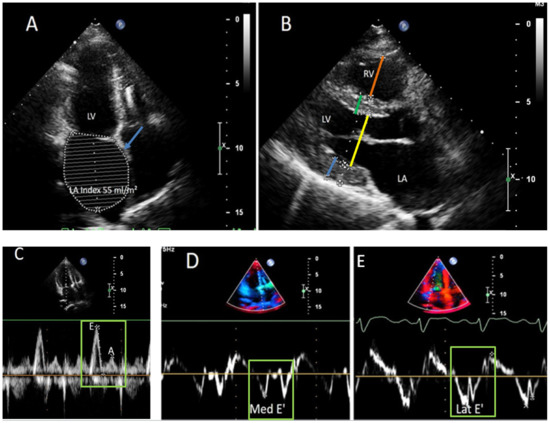

ECHO revealed moderate hypertrophy of the left ventricle (LV, septum, and posterior wall 1.4 cm), left atrium (LA) dilatation up to 112 mL and diastolic dysfunction with a restrictive filling pattern. Ejection fraction (EF) of LV was preserved (66%). To rule out the glycogen storage disease, the activity of lysosomal enzymes was assessed: all indexes were normal. As well, a

cardiac MRI was performed: LV EF 53%, interventricular septum 1.2 cm, LA 200 mL, diffuse accumulation of contrast with thickened endocardium (3–4 mm) of both left and right ventricles, site of intramyocardial late gadolinium enhancement (LGE) in LV were observed.

ECHO confirmed the presence of restrictive cardiomyopathy with hyperechogenic and layered LV myocardium, which could be the sign of storage disease (

Figure 2,

Supplementary Videos S1 and S2).

ECHO did not show any significant dynamics.